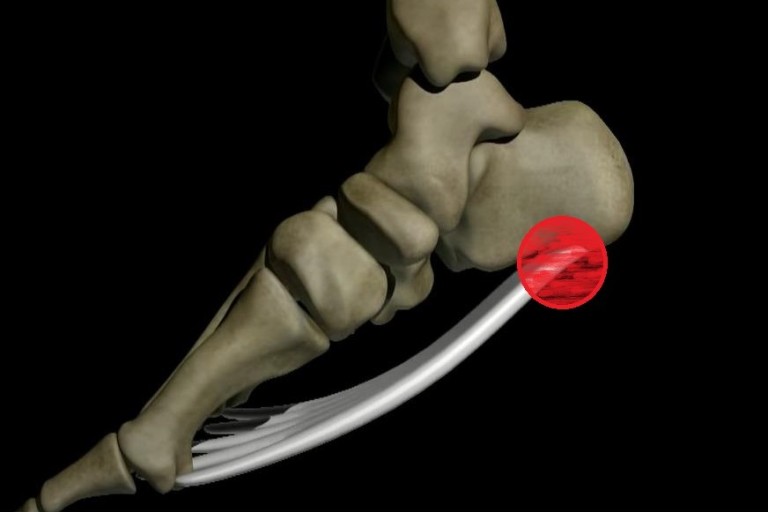

초기에는 밤에만 불편함을 느끼다가 점점 지속 시간도 늘어납니다.3. 족저근막염

발바닥 통증의 대표 질환으로,

발뒤꿈치에서 발바닥 전체로 이어지는 근막에 염증이 생기며

걷거나 서 있을 때 발바닥이 뜨겁고 찌릿한 통증을 유발합니다.

특히 아침에 첫 발을 디딜 때 더 아픈 경우가 많아요.